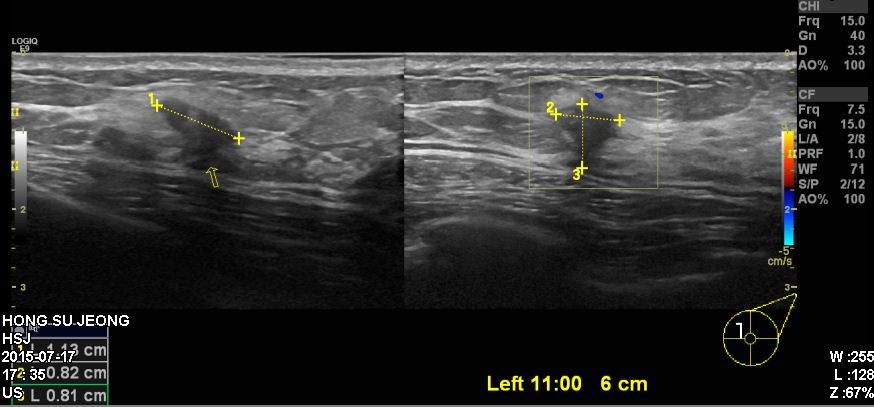

좌측에 만저지는 몽우리로 타원 진료 후 조직검사 의뢰 받아 내원하신 40대 여성 분으로

본원에서 좌측 11시 방향에서 6cm 떨어진 거리의 있는 혹을 조직검사 시행 하여

침윤성유관암 진단 되었습니다.